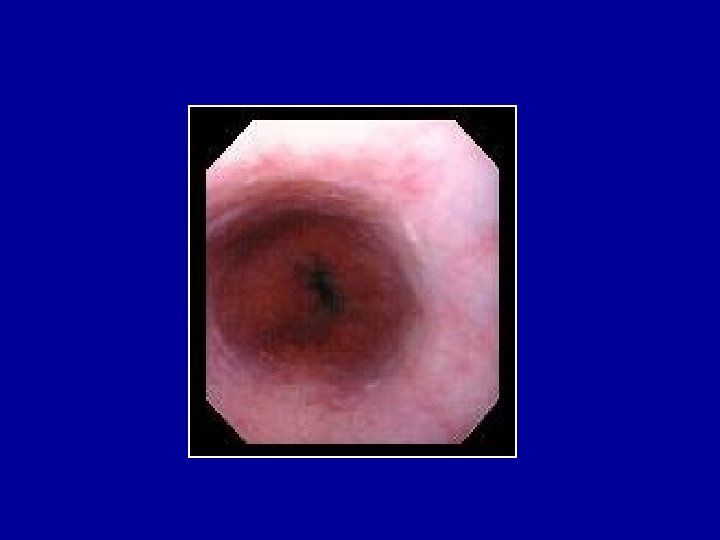

STENOSE PEPTIQUE

OESOPHAGITES INFECTIEUSES

CANCERS